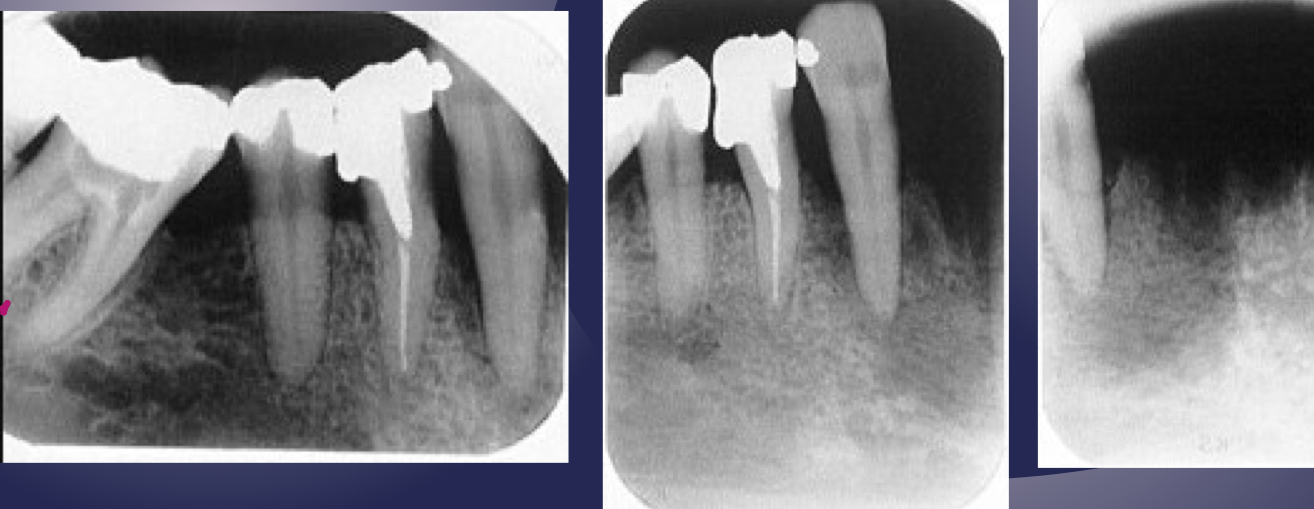

which osteomyelitis phase?

internal structure:

sequestration, sinus tract or fracture

acute

white and black arrow

some effects on surrounding structures:

bone formation, periosteal stimulation = onion skin

bone resorption

periosteal reaction

new bone formation parallel to the cortex (almost looks like periosteum lifted and bone under)

proliferative periostitis and the onion skin periosteal reaction have the same radiographic appearance

true

fistulous/sinus tract